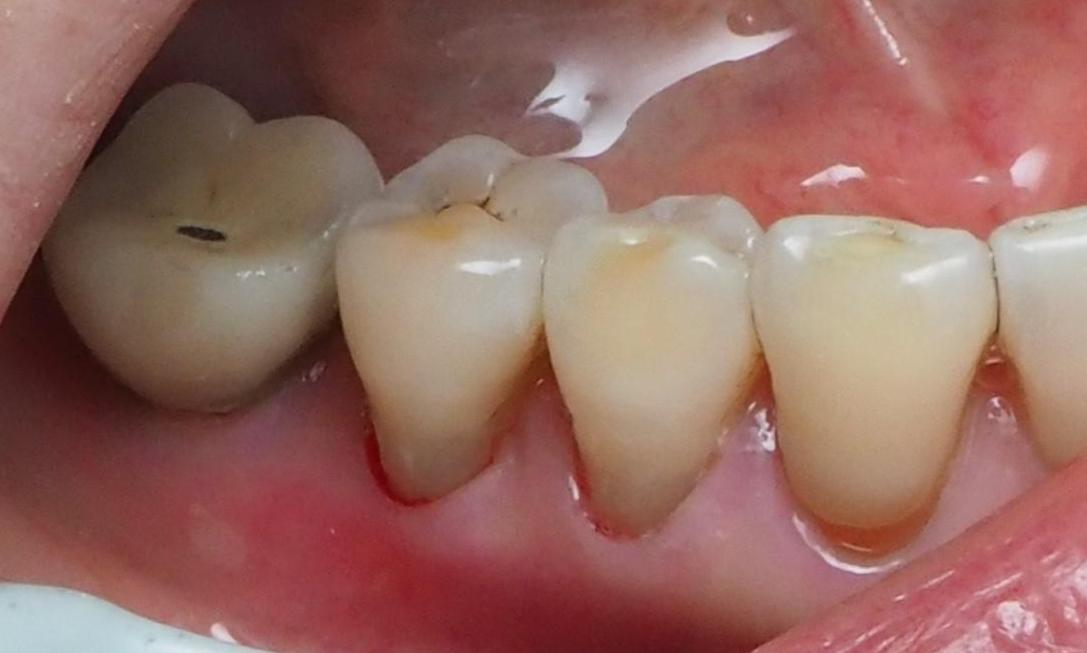

Mrs. J. didn't know anything could be done for the discolored wear areas on her back teeth. After one visit with Dr. Karian, these teeth are reinforced and beautiful again!